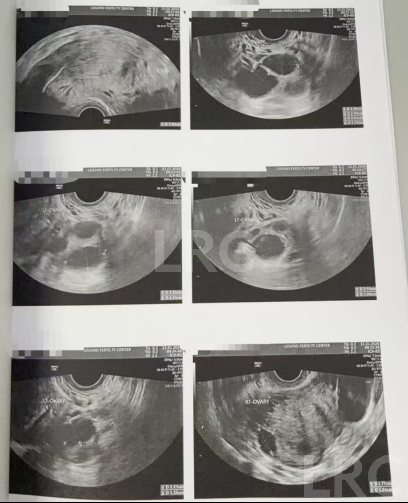

促排第六天

阴超检查(只数能用卵子):

- 右侧卵泡 6 颗 (14,11,9,9,8mm)

- 左侧卵泡 5 颗 (14,14,13,11,11mm)

激素水平检查:

- 促黄体生成素 3.60 miu/ml

- 雌二醇 313 pg/ml

促排第十天

阴超检查:

- 右侧卵泡 4 颗 (18,18,16,13mm)

- 左侧卵泡 6 颗 (22,21,20,20,17,13mm)

子宫内膜厚度:10.2 mm